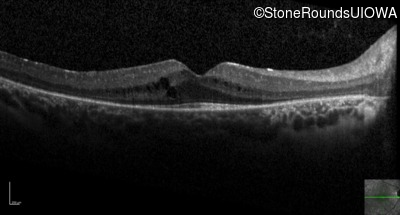

Optical Coherence Tomography - Left - 20/32

Exemplar / OCT Stack